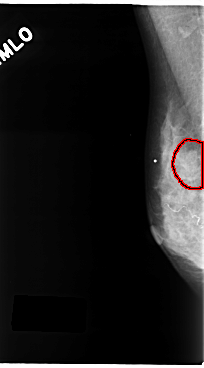

C_0125_1.RIGHT_MLO

RIGHT_MLO LINES 4784 PIXELS_PER_LINE 2640 BITS_PER_PIXEL 12 RESOLUTION 50 OVERLAY

FILE: C_0125_1.RIGHT_MLO.OVERLAY

TOTAL_ABNORMALITIES 1

ABNORMALITY 1

LESION_TYPE MASS SHAPE OVAL MARGINS ILL_DEFINED

ASSESSMENT 4

SUBTLETY 3

PATHOLOGY MALIGNANT

TOTAL_OUTLINES 1

BOUNDARY